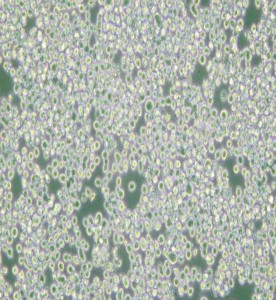

RPMI 8226人多發性骨髓瘤外周血B淋巴細胞主圖

RPMI 8226人多發性骨髓瘤外周血B淋巴細胞

中文名稱 :人多發性骨髓瘤外周血B淋巴細胞

細胞簡稱 :RPM I8226

細胞形態 :淋巴母細胞樣

生長特性 :懸浮細胞